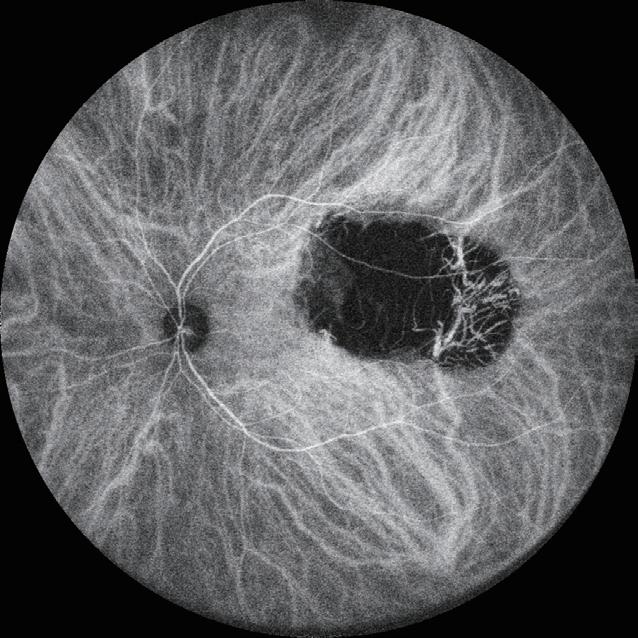

29 Preserving Foveal Function in Geographic Atrophy

Usha Chakravarthy MD, PhD